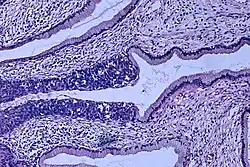

Histopathologic image (H&E stain) of carcinoma in situ (also called CIN3), stage 0: The normal architecture of stratified squamous epithelium is replaced by irregular cells that extend throughout its full thickness. Normal columnar epithelium is also seen.

Cervical intraepithelial neoplasia, the potential precursor to cervical cancer, is often diagnosed on examination of cervical biopsies by a pathologist. For premalignant dysplastic changes, cervical intraepithelial neoplasia grading is used.

The naming and histologic classification of cervical carcinoma precursor lesions has changed many times over the 20th century. The World Health Organization classification[49][50] system was descriptive of the lesions, naming them mild, moderate, or severe dysplasia or carcinoma in situ (CIS). The term cervical intraepithelial neoplasia (CIN) was developed to place emphasis on the spectrum of abnormality in these lesions, and to help standardize treatment.[50] It classifies mild dysplasia as CIN1, moderate dysplasia as CIN2, and severe dysplasia and CIS as CIN3. More recently, CIN2 and CIN3 have been combined into CIN2/3. These results are what a pathologist might report from a biopsy.